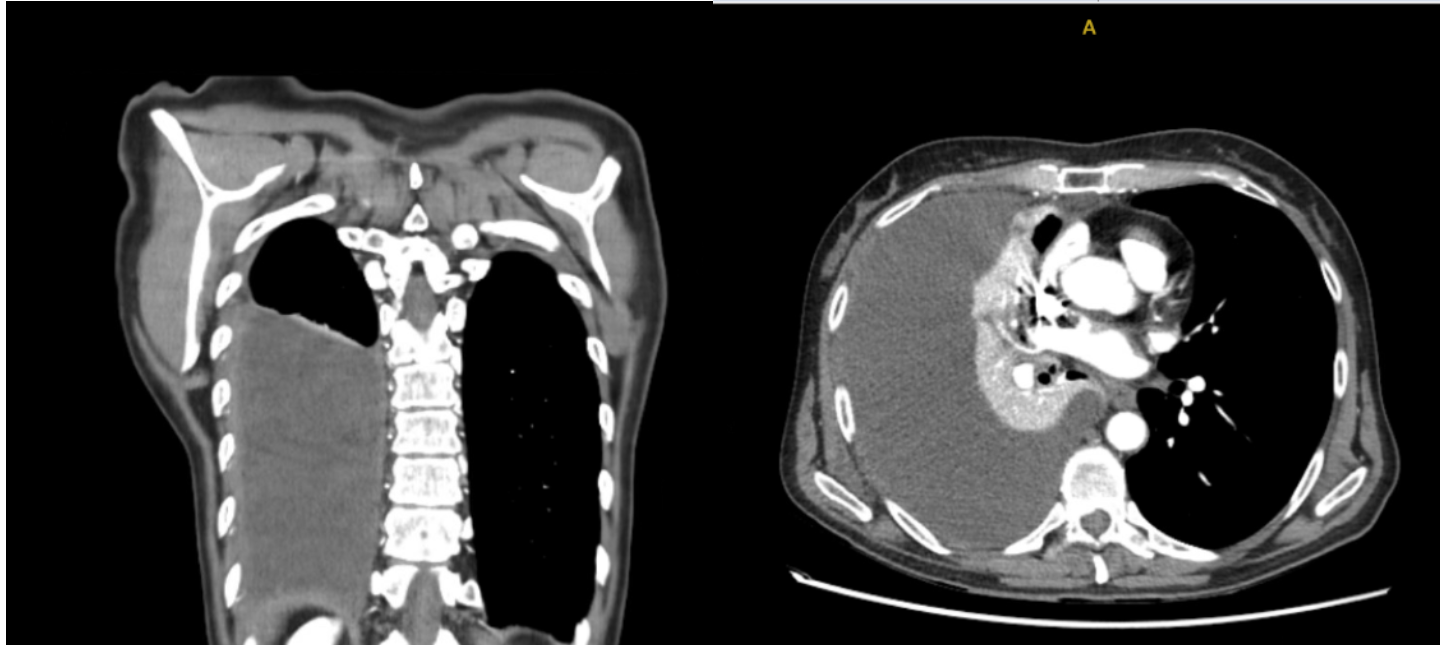

En urgencias hospitalarias: Dímero D 1400 , sin leucocitosis, Radiografía de tórax derrame pleural derecho, Angiografía pulmonar: descarta TEP. Moderado/severo derrame pleural derecho con atelectasia pasiva.

Múltiples toracocentesis diagnósticas/evacuadoras total de 1,08 litros y con líquido pleural tipo exudado linfocítico; microbiología y citología negativa. Ecografía pulmonar control: persistencia de DP y aumento de tabicación. Tomografía abdomino pélvico confirma persistencia de derrame. Analítica destaca PCR y Procalcitonina elevadas. Nueva toraconcentésis ecodirigida: líquido pútrido, cultivo de DP: positiva para Parvimonas micra Fusobacterium nucleatum. Antígeno orina positivo: neumococo. Inicia Piperacilina/Tazobactam e inserción drenaje pleural con aspiración e instilación de urokinasa durante 10 días.